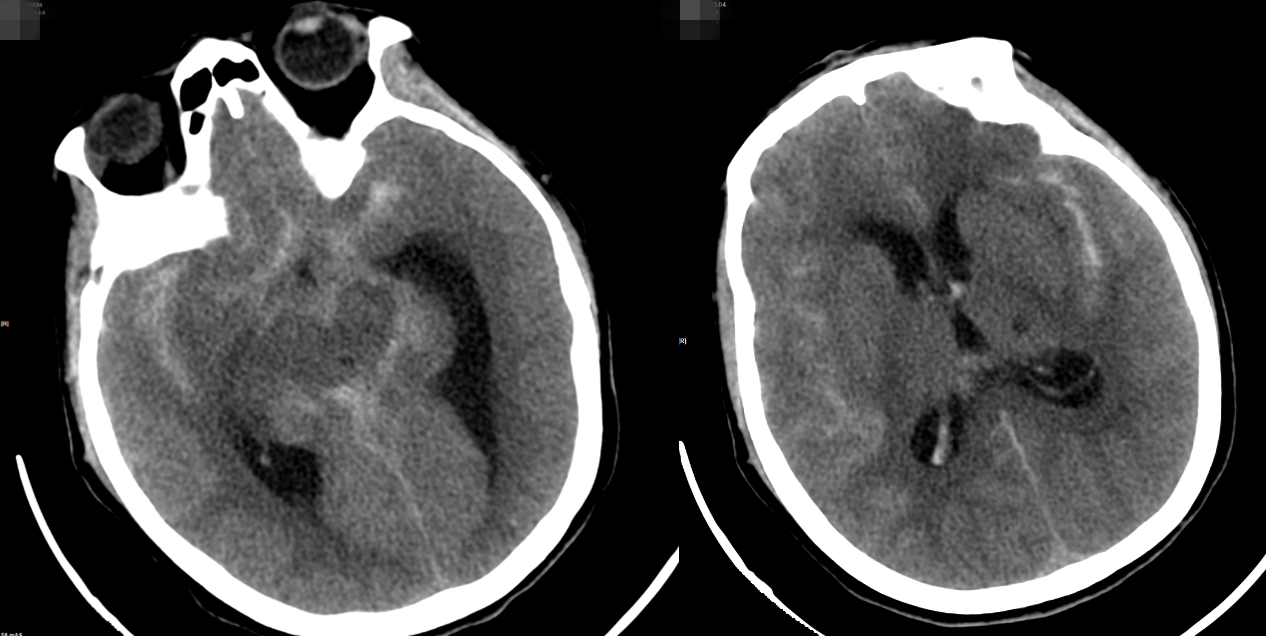

救护车到达医院时,介入医学科、重症监护室等科室的医生已经在急诊科门口等候。通过头部CT和CTA检查,发现患者存在蛛网膜下腔出血、梗阻性脑积水、脑室积血等危急情况。

头CT显示:蛛网膜下腔出血,脑室积血

CTA:动脉瘤位置

结合影像学表现和多年的诊断和治疗经验,干预医学科负责人、副主任医师唐汝军迅速判断脑出血的主要原因是颅内动脉瘤破裂出血。